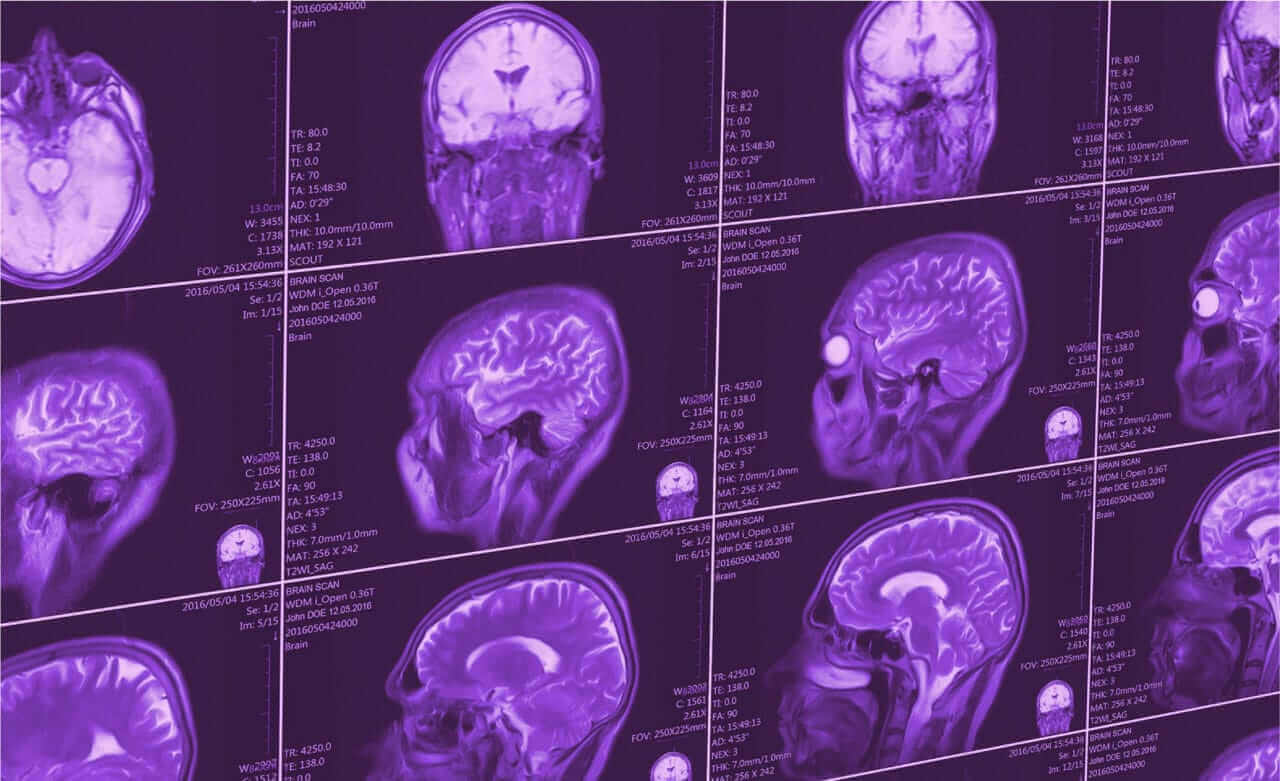

QBI at UCSF holds exemplary human and preclinical imaging research services offered by the Department of Radiology and Biomedical Imaging.

Over the past several years, significant time and effort was spent in building what is a world-class facility for medical imaging research in the Bay Area. Continuing the long tradition of research excellence, state-of-the-art imaging systems have been deployed to provide the ability for multi-modal and cutting edge in vivo assessment of tissue structure, biochemistry, molecular biology and function.

In addition, streamlined processes have been developed, that are aimed at lowering the barrier-to-entry for imaging related investigation of health and disease. The Department of Radiology and Biomedical Imaging can provide comprehensive services, starting with study design and sample/subject management, and ranging to data analysis and post-processing.